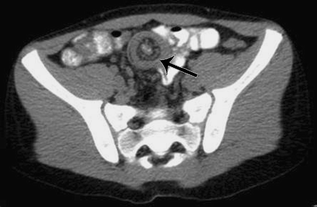

On physical exam, the child was afebrile with stable vital signs and was in mild distress secondary to pain. The abdomen was soft with hyperactive bowel sounds and non-specific right lower abdominal quadrant tenderness. Obturator, psoas, Murphy’s and Rovsing’s signs were all negative. On digital rectal exam, the rectal vault was empty and stool tested guaiac negative. A CT of the abdomen and pelvis was obtained and demonstrated the classic target sign of intussusception in both the longitudinal and transverse planes (Figs. 1 and 2). Exploratory laparotomy was performed, the intussusception was located and reduced, and a 1.5 × 1.5 × 1.5-cm Meckel’s diverticulum was identified as the lead point and excised.

The target sign is classic for intussusception on both CT and ultrasound. Its appearance is attributed to the different densities of tissue layers that are apposed to each other by the telescoping bowel, and when the luminal diameter is increased, intussusception must be considered in the differential diagnosis [1]. Although most cases of intussusception are idiopathic, there have been several case reports of Meckel’s diverticulum serving as a lead point [2–4].